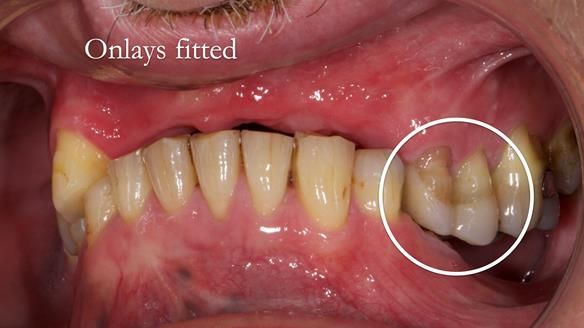

Keith’s case was one of the most challenging and rewarding cases I’ve treated this year. This 64 year old man presented with ill-fitting acrylic partial dentures that lacked stability, retention, and aesthetics. They constantly broke. He had lost the upper front teeth in a road traffic accident in his early 20s. The unopposed teeth had erupted, taking up space. After careful planning, we made a durable, metal-based upper partial denture/splint to address his dental concerns. He loved the outcome.

2. Onlay preparations: Composite onlays were fitted for his upper left premolars to repair these teeth and support the new denture.

I also used the Dahl concept to re-establish the occlusion upon fitting the RPD, which helped to intrude the lower left canine without needing to grind it too much.